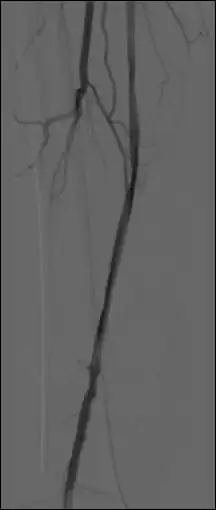

Rozpoznanie jest ustalane na podstawie obrazu klinicznego. Badania obrazowe mają charakter pomocniczy i nie mogą opóźniać zabiegu ratującego kończynę. Ultrasonografia z badaniem dopplerowskim może pozwolić wykazać ograniczenie lub brak przepływu w chorej kończynie, a także może uwidocznić miejsce niedrożności. Najbardziej przydatnym badaniem jest angiografia. Umożliwia lokalizację niedrożności, często pozwala na różnicowanie zakrzepu od zatoru i jest pomocna w kwalifikacji chorych do leczenia inwazyjnego[9]. Konieczne jest wykonanie podstawowych badań laboratoryjnych oraz EKG i RTG klatki piersiowej[10].